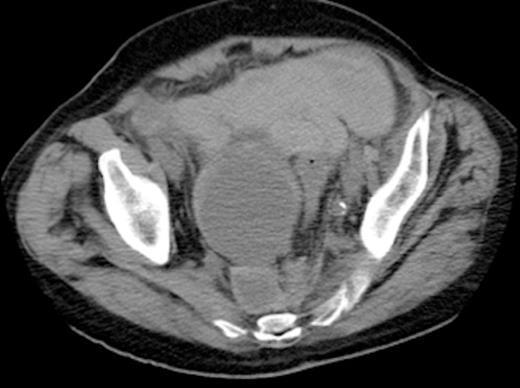

Axial view of CT abdomen-pelvis showing right internal iliac artery aneurysm with a contained pre-sacral leak (as indicated by arrow)

The patient deteriorated the following day, becoming hypotensive and anuric, with an increasingly tender abdomen. Haemoglobin levels dropped substantially and he developed a lactic acidosis. After initial resuscitation, an urgent CT scan of the chest, abdomen and pelvis showed an 8.5cm aneurysm of the right internal iliac artery. There appeared to be a contained leak from the aneurysm in the pre-sacral region (Fig. 1). A moderate amount of intraperitoneal free fluid was noted. A right sided hydronephrosis with associated right hydroureter was also noted.